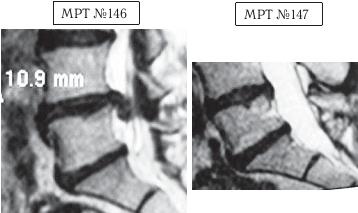

На МРТ №146 в поясничном отделе позвоночника наблюдается секвестрированная грыжа межпозвонкового диска в сегменте LIV-LV с разрывом задней продольной связки. На МРТ № 147 наблюдается результат после одного курса лечения методом вертеброревитологии. Этот случай особо запомнился своей сложностью, а также большим желанием данного человека восстановить утраченное здоровье. ![]() На МРТ № 148 наблюдается состояние поясничного отдела позвоночника после хирургических операций: рецидив грыжи межпозвонкового диска в сегменте LV-SI, осложнённой массивным секвестром с краниальной миграцией. Размер грыжи до 15 мм дорсально (кзади) и до 34 мм — краниально (вверх). На МРТ № 149 наблюдается состояние поясничного отдела позвоночника после одного курса лечения методом вертеброревитологии. Вот ещё один любопытный результат из этого раздела документальной медицинской информации, который заслуживает внимания.